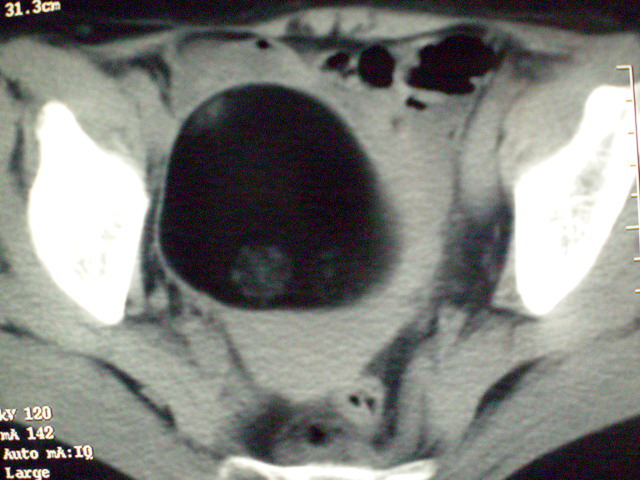

f 60y,b超提示脂肪瘤.[img][/img]

右侧附件囊性畸胎瘤,三种组织均见.

那个高密度灶形状好象牙齿。典型,收藏了

脂肪密度肿块,内可见团块状影,典型皮样囊肿

的确比较典型的畸胎瘤!不过,应该确切的说是盆腔畸胎瘤,右侧附件来源的可能性比较大。